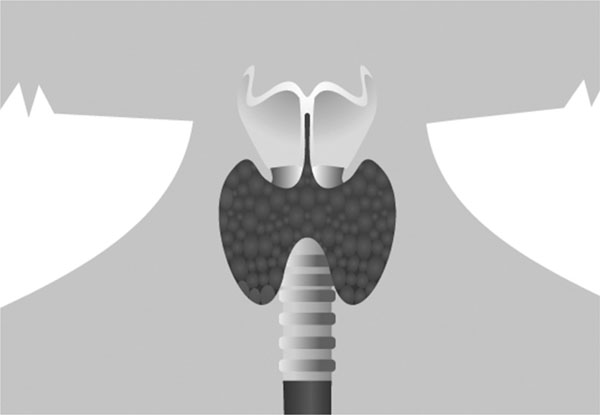

Постановка пиявок на щитовидную железу

Восьмая постановка – работа с щитовидной железой. Уделим ей повышенное внимание, ибо система эндокринологии «в ответе» практически за любой сбой в организме. Гормоны щитовидной железы необходимы: для нормального умственного и физического развития их недостаток в детском возрасте приводит к прекращению роста, а при беременности – к недоразвитию мозга будущего ребенка; для регулирования водно-солевого баланса и образования некоторых витаминов (например, витамина А в печени); для нормального развития молочных желез у женщин и правильной работы клеток иммунной системы.

Здоровье щитовидной железы, оптимальный уровень ее гормонов – необходимые условия для хорошего психологического самочувствия человека и его физического состояния, в том числе и веса. Щитовидная железа расположена на передней поверхности шеи, спереди от трахеи. Она имеет форму бабочки. Щитовидная железа является единственным органом, синтезирующим органические вещества, содержащие йод. Это железа внутренней секреции, вырабатывающая гормоны тироксин (Т4) и трийодтиронин (Т3). Они участвуют в обмене веществ и энергии, процессах роста, созревания тканей и органов. Также в щитовидной железе производится гормон кальцитонин. Он участвует в образовании новой костной ткани. Щитовидная железа вырабатывает много гормонов – все они жизненно важны как для психического, так и для физического состояния организма. Деятельность щитовидной железы по выработке гормонов регулируется высшими центрами: гипофизом, гипоталамусом и центральной нервной системой (ЦНС). Щитовидная железа – «управление красотой». Когда с ней все в порядке – у вас всегда блестящие глаза, роскошные волосы, крепкие ногти, упругая чистая кожа и свежее лицо. А еще нормальный вес, стройная фигура, никаких проблем с женским циклом и море энергии и отличного настроения!

Щитовидная железа – самый кровоснабжаемый орган: на единицу объема за единицу времени крови через щитовидную железу протекает больше, чем через мозг. Это значит, что щитовидная железа весьма чувствительна к нарушению кровообращения. Поэтому гирудотерапия – первая помощница для нее! Клеточное голодание вследствие диет, неправильного или недостаточного питания приводит к нарушению структуры белков щитовидной железы и, соответственно, синтеза гормонов.

Щитовидная железа – самый кровоснабжаемый орган.